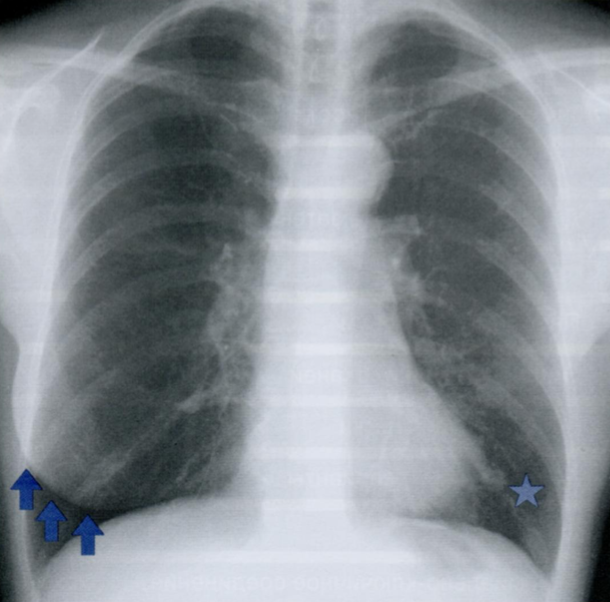

Оцените ассиметричность мягких тканей на снимке.

Обратите внимание на тень молочной железы (стрелочки), оцените симметричность теней слева и справа.

Ассиметрия прозрачности может наблюдаться после мастэктомий, радикального иссечения шейных лимфатических узлов, посттравматической гематомы грудной стенки, гепертрофии/атрофии мышц.

Пациентка после левосторонней мастэктомии с просветлением в нижних отделах с соотвествующей стороны (звездочка) в связи с отсутствием молочной железы (стрелочки).

Если есть сомнения, можно внимательнее рассмотреть подмышечную область на предмет возможного наличия металических клипс после иссечения ЛУ подмышечной впадины (фото ниже).

Ключевой момент - не ошибиться, принимая уменьшение прозрачности с одной стороны за выпот или внутрилегочное образование.